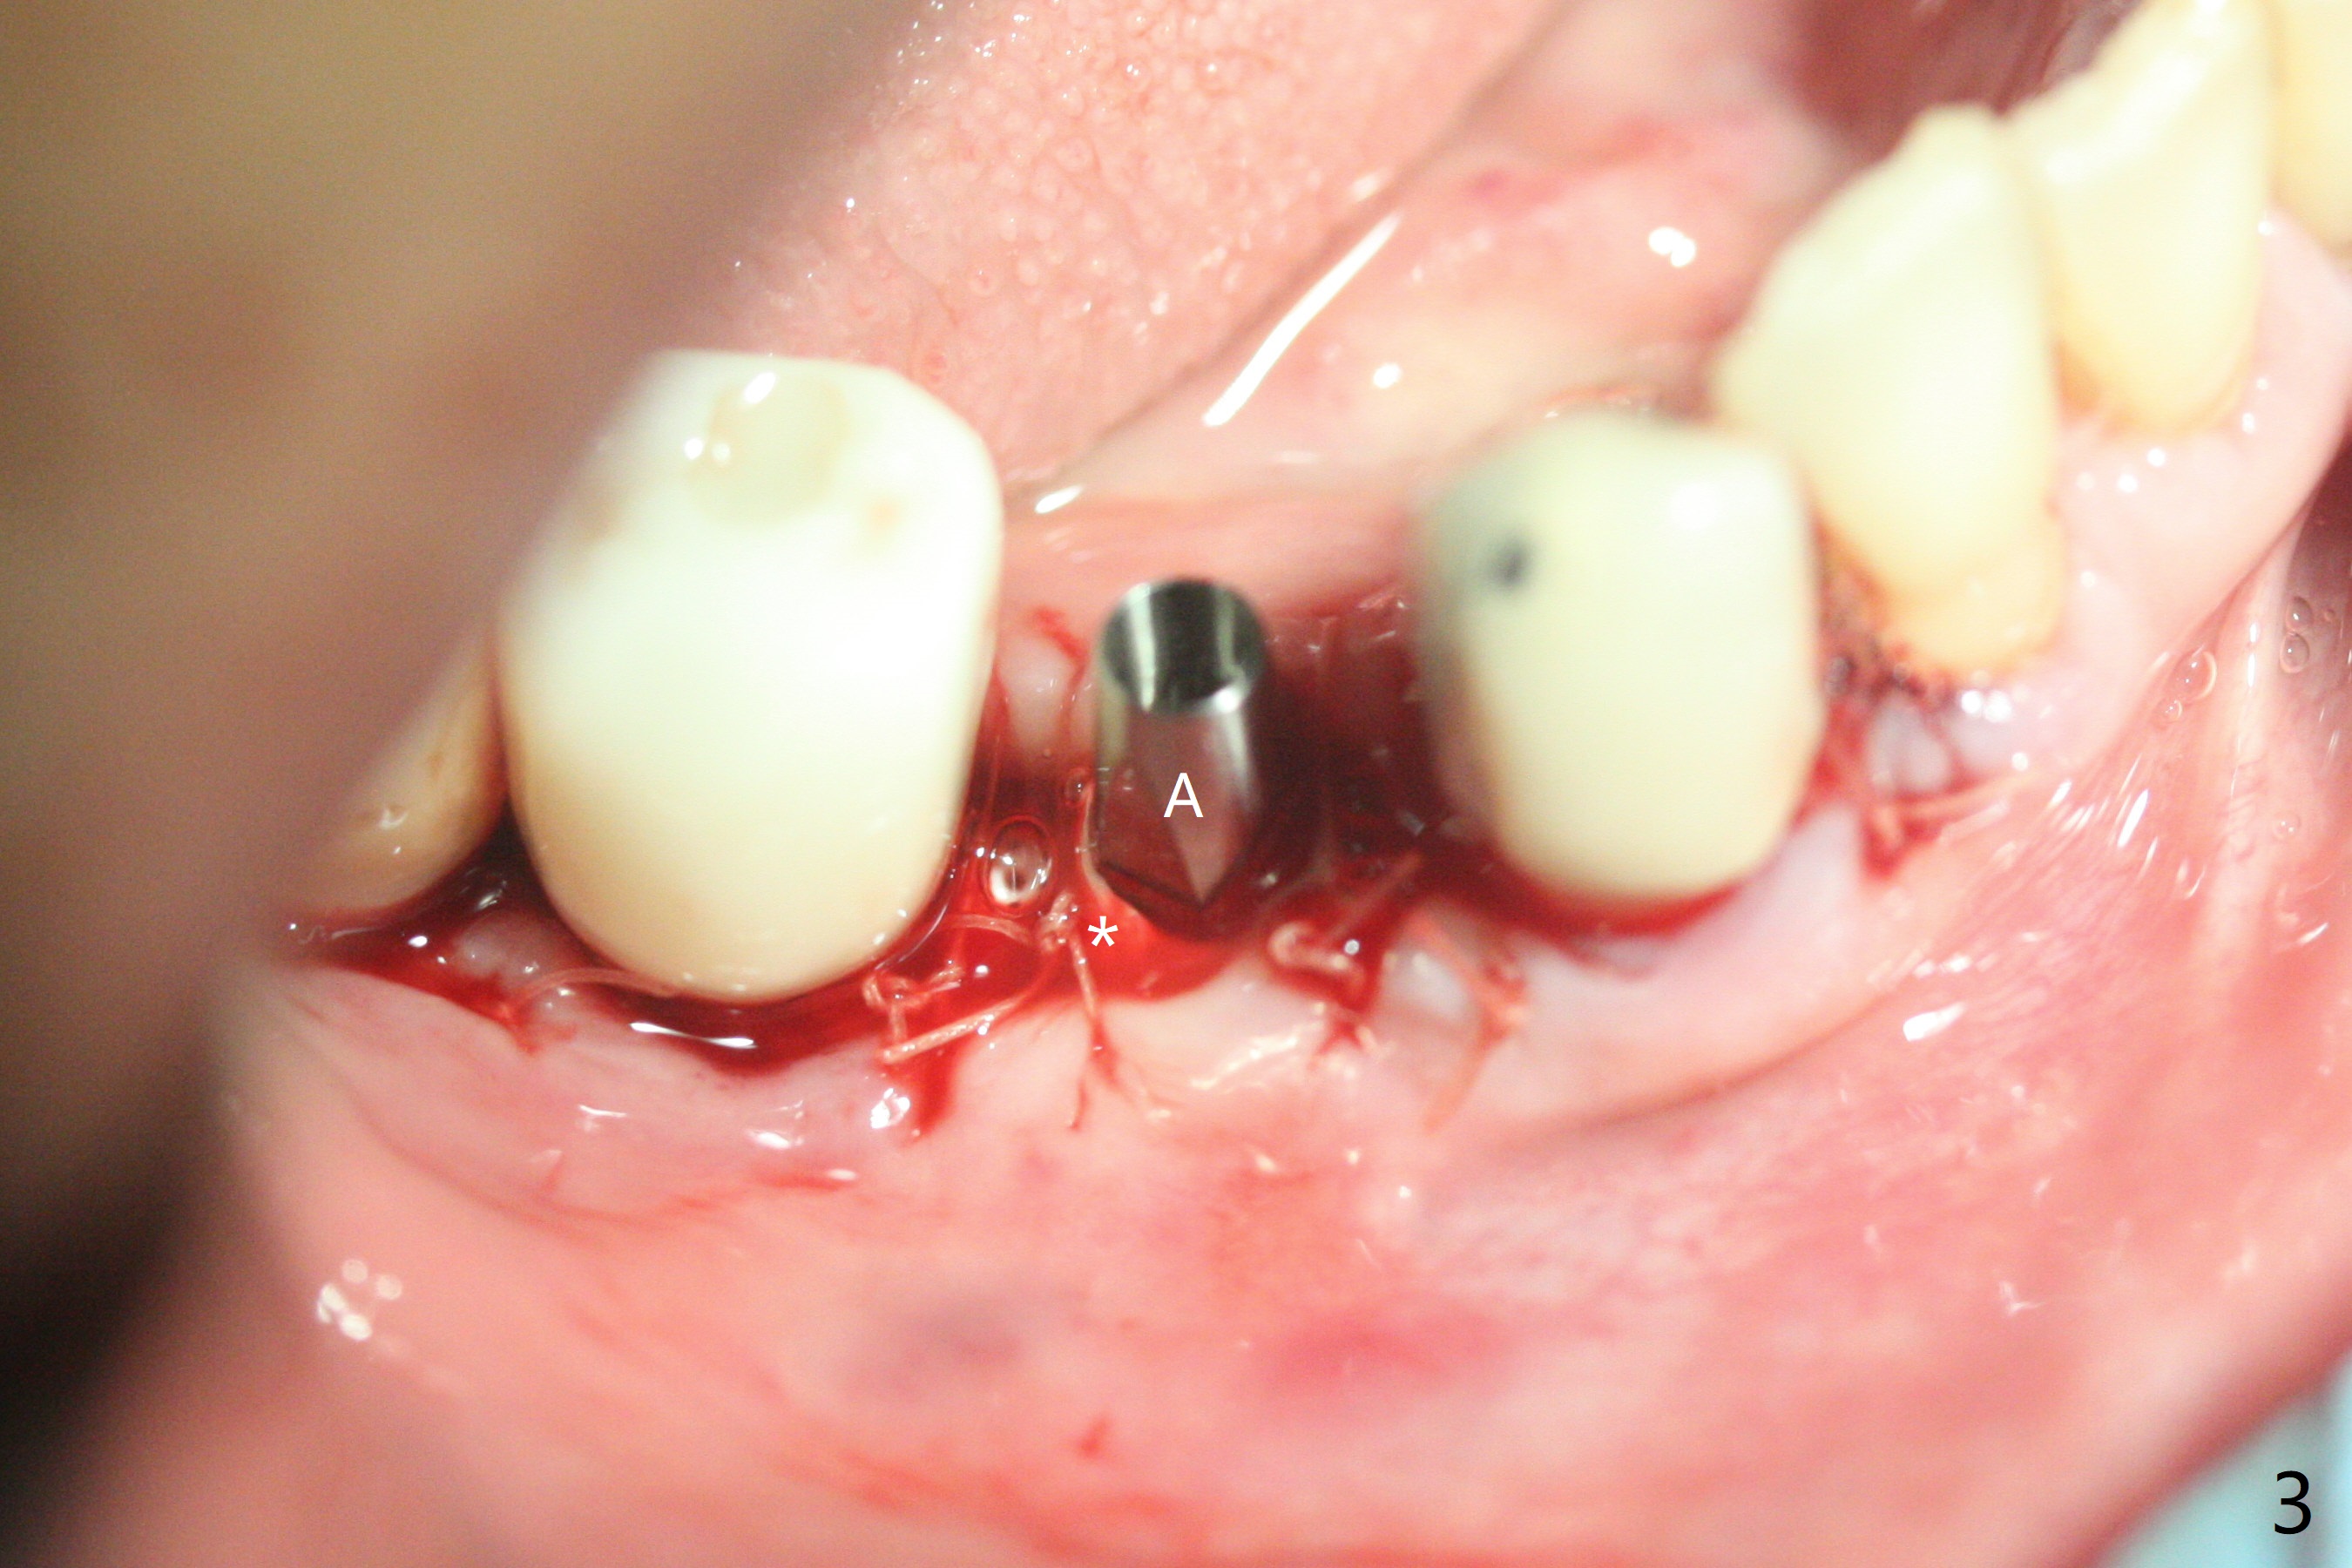

28牙位3.5x8.5毫米植体导板植入后,颊侧远中螺纹暴露,为了植骨,附近骨壁钻洞创造出血点以及放置基台(图一:5x7.5(3)毫米)。放置粘性骨粉后(图二:*),覆盖薄层PRF,后者可能很快吸收,为了防止骨粉暴露,放置不可吸收膜(图三:*),当中打洞,穿过基台固定,表面缝合。术后六周不可吸收膜部分暴露(图四)。图五,六显示在取出时膜当中固定用的洞,下面伤口愈合正常(图七)。